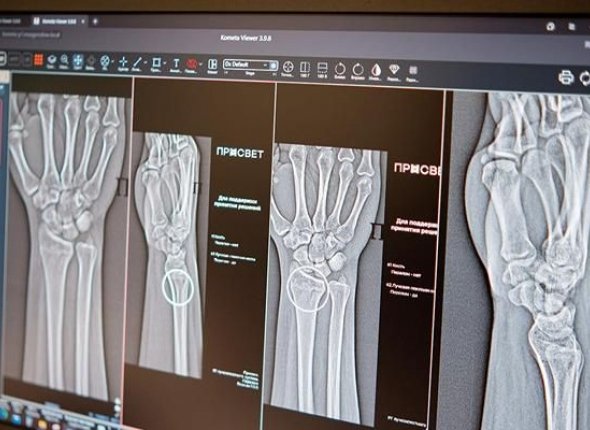

Тематическое фото

Две новые системы на основе искусственного интеллекта начали работать в медучреждения Москвы. Они способы с высочайшей точностью выявлять сложные травмы опорно-двигательного аппарата. Об этом сообщается на сайте mos.ru.

Как рассказала заммэра Москвы по социальным вопросам Анастасия Ракова, в арсенале столичных рентгенологов появились два новых ИИ-сервиса. Они специализируются на диагностике множественных переломов голеностопного и лучезапястного суставов. Как отметила Ракова, эти части тела относятся к числу наиболее функциональных и одновременно уязвимых элементов скелета.

"Алгоритмы автоматически отметят поврежденные участки и выполнят необходимые измерения, даже если на снимке присутствуют признаки сразу нескольких переломов", — сказала Ракова.

По словам главного внештатного специалиста по лучевой диагностике Москвы Юрия Васильева, новые технологии особенно востребованы при травмах предплечья, кисти и голени. По его словам, ИИ-алгоритм работает как интеллектуальный помощник, повышающий точность и скорость анализа изображений. Это позволяет оперативно назначить лечение и избежать осложнений.